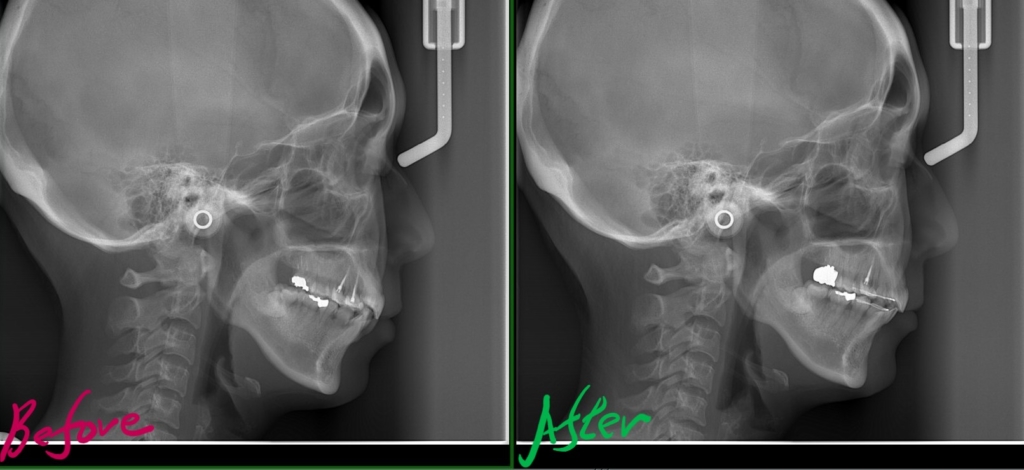

レントゲン写真でも矯正治療前後を比較してみましょう

上のレントゲン写真で見るよりも、顔写真で見る方が矯正後の口元がスッキリしたことが分かります